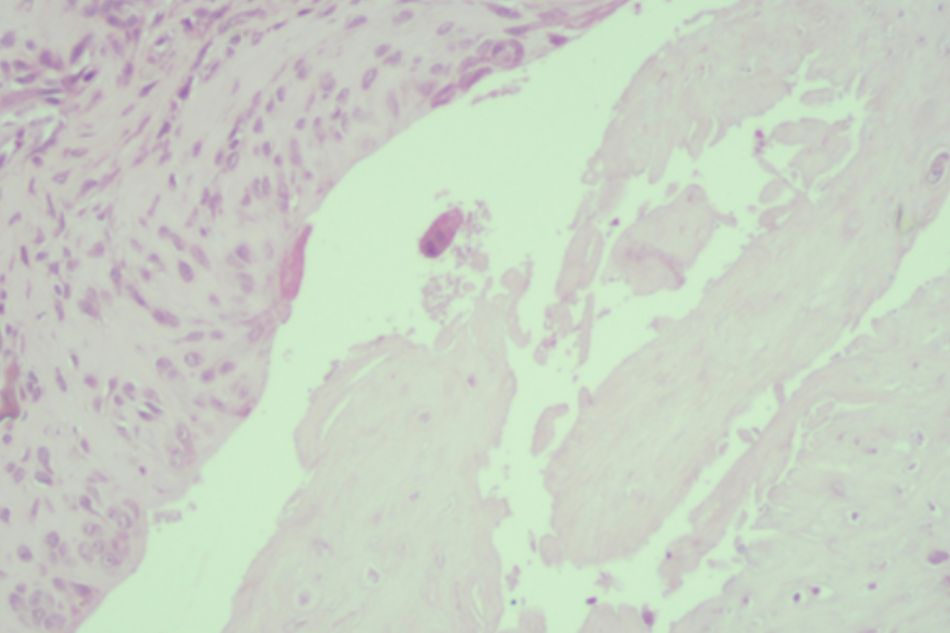

Figure 2.3. Knee joint sample in Group II (rat no.11)

Moderate subchondral bone and cartilage damage

Figure 2.4. Knee joint sample in Group II (rat no.12)